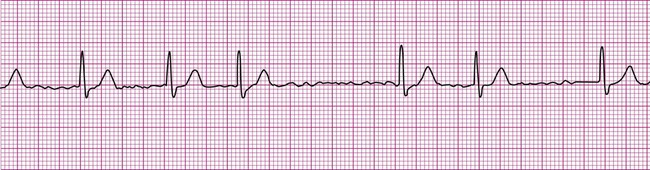

Normally, a cardiac impulse is generated by the SA node, causing atrial depolarization. This is followed by a slight delay in the AV node, after which the impulse is conducted to the ventricles, causing ventricular depolarization. These events are shown in Figure 12-7 in their normal spatial and temporal sequence and in normal sinus rhythm. A P wave precedes every QRS complex and every P wave is, in turn, succeeded by a QRS complex. This occurs within an interval of 0.12 to 0.20 second (one large box), as determined by the P-R interval. The QRS complexes occur within a range of 0.04 to 0.12 second, indicating that ventricular impulse conduction and depolarization is occurring in a normal interval. The positively deflected T wave indicates normal ventricular repolarization. Because the SA node spontaneously depolarizes at a rate of between 60 and 100 beats per minute, the rate of normal sinus rhythm must fall within these limits.